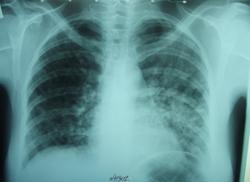

Направили с села женщину, 1969 г.р. Диагноз дежурный - Хронический бронхит.

На фоне полисегментарной пневмонии прослеживается, на мой взгляд, какая- то очаговая двусторонняя диссеминация (а анамнез, клиника поподробнее не известны?). Если с таким диагнозом направили, думаю след. шаг - контроль после курса терапии + КТ + онколог на всякий пожарный (может мтс-ы какие?)

дифдиагностика диссеминаций. Два диагноза. В первую очередь следует подтвердить или исключить подострый диссеминированный туберкулез, который можно излечить. Следует думать и о карциноматозе. В этом согласен с тактикой обследования предложенной Пантелеймоном. Томографировать надо.

исследования на туберкулез, бронхоскопия с биопсией и мн. другое. Так как возможности ограничены больницы , где автор работает необходимо направить пациентку в ПТД. На представленных томограммах (см. рисунки) полости распада, что не исключает специфический генез заболевания.

Попробую еще поддержать версию онко, клиника по-моему это подтверждает, высокий СОЭ тоже. Если бы это был тбц, то с лета, когда у пациентки появились жалобы, он бы уже много чего в легких наделал. Распада на томограмме я не вижу возможно очаги так наложились. Наличие жалоб при нормальной флюорограмме с последующей динамикой говорит о том, что летом вероятнее всего уже были интерстициальные изменения, но предел метода не позволил их увидеть.

Насчет ассиметрии - для онко конечно не характерно, но и для гематогенного тбц тоже. Если путь распространения лимфогенный, то метастазирование тоже могло произойти не единовременно.

Четкие очаги видны на боковых снимках, просто их много + лимфангит, поэтому на прямом мазня. Возможно, метастазирует из м.ж. или щ.ж

Версию Твс поддержу. Он самый. Только уже не диссеминированный, а инфильтративный, и будет с распадом (если ещё не уже).:(

Это и есть скорее всего инфильтративный туберкулез в/д(S3,Sязычк.?)и возм.S6?н/д левого легкого-тмг,к сожалению,не те),ф распада и обсеменения(диссеминированный по распространенности).МВТ-?Подождем результатов

Высока вероятность туберкулёза.Бок и томограммы.Но тени очень "туберные".

Появилась информация от лечащего врача(видел его сегодня), что женщину выписали и тубер исключили, он сказал, что будет далее её обследовать.